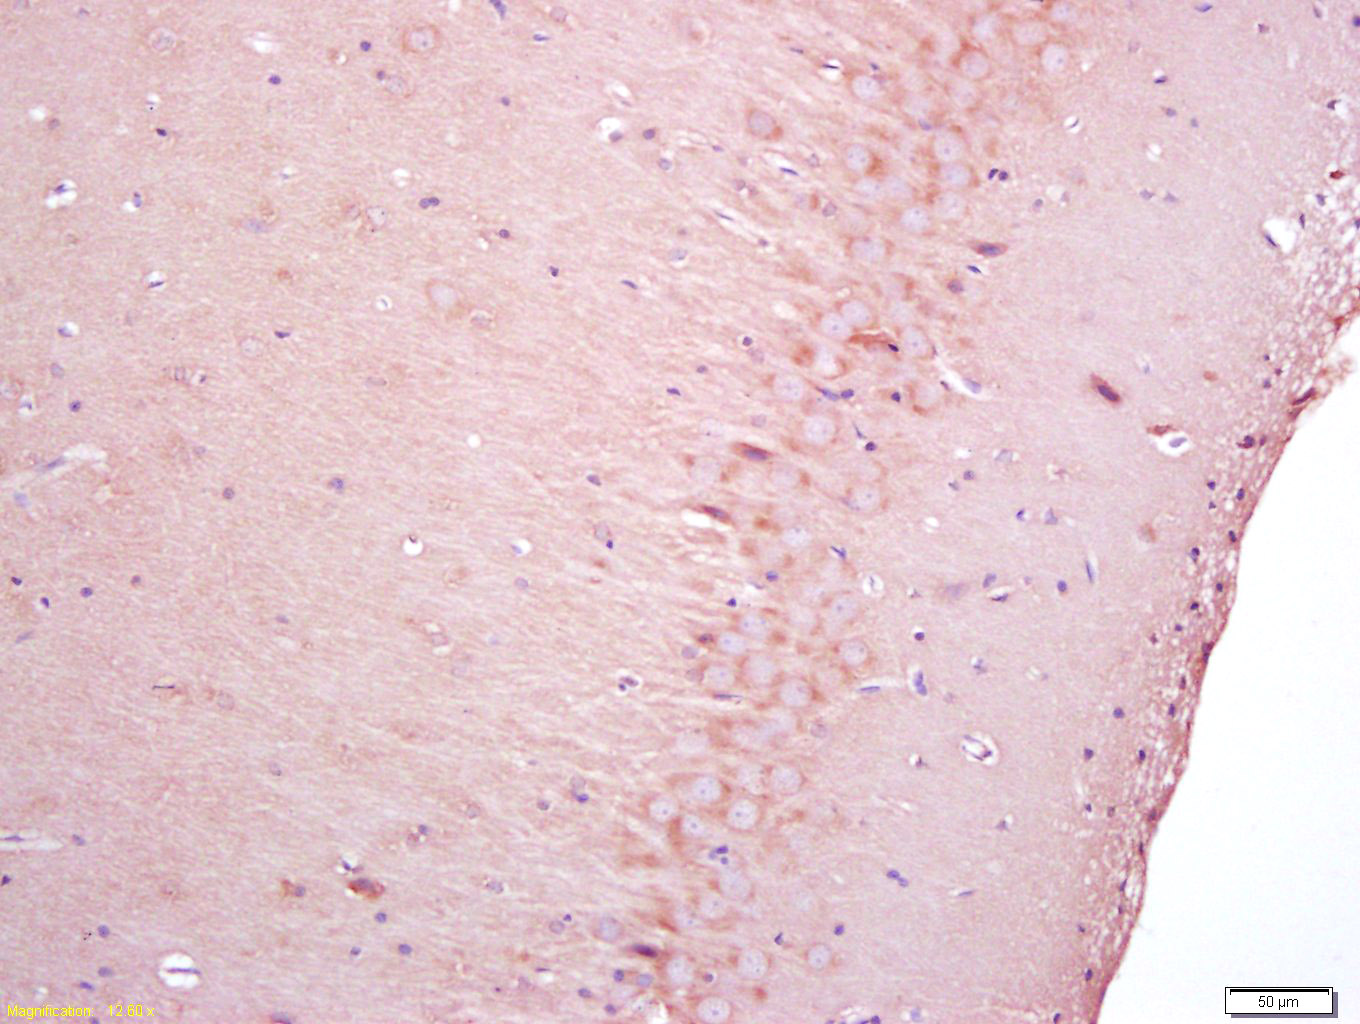

Antigen retrieval: citrate buffer ( 0.01M, pH 6.0 ), Boiling bathing for 15min; Block endogenous peroxidase by 3% Hydrogen peroxide for 30min; Blocking buffer (normal goat serum,C-0005) at 37℃ for 20 min;

Incubation: Anti-NGFR Polyclonal Antibody, Unconjugated(bs-7122R) 1:200, overnight at 4°C, followed by conjugation to the secondary antibody(SP-0023) and DAB(C-0010) staining